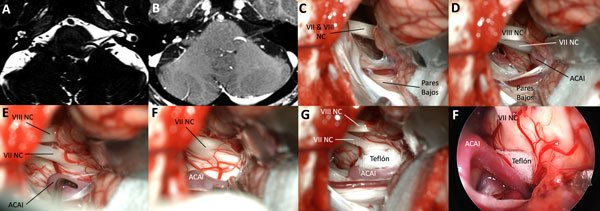

Figura 1. Al ingresar a la cisterna del ángulo pontocerebeloso se observa el flóculo obstruyendo la visión del sitio de salida real del nervio facial (A y B). La disección aracnoidea del floculo desde la cisterna de los pares bajos permite la retracción desde caudal a rostral que limita el estiramiento latero-medial (C y D). Se identifica la arteria cerebelosa anteroinferior; se la reclina y separa del nervio, interponiendo una lámina de teflón (E y F).

Figura 2. En ocasiones, para lograr una efectiva retracción ascendente del flóculo, se requiere disecar el plexo coroideo. El VII par suele estar anatómicamente anterior e inferior en el paquete, por lo que identificarlo desde abajo en el sitio de salida del tronco es la manera correcta de reconocer el conflicto, en este caso originado por la arteria cerebelosa anteroinferior.